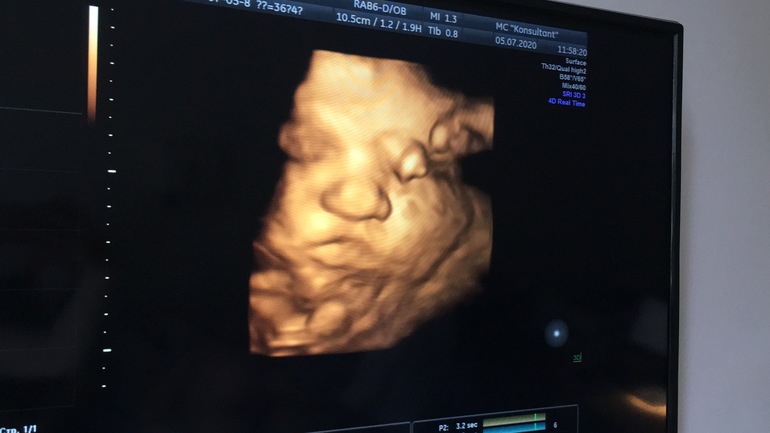

Вопросы про УЗИ, обследования и анализы: что, где, как, когда?Ура состоялось наше узи! Так ждала я и хотела посмотреть на эти щечки, Хотелось целовать экран.

Как мило было смотреть на узи как она пальцы сосет, пуповину тоже сосет, сморщивается и тогда щеки еще больше, а пальчики как сосиски в перетяжках! 😆

Какие щечки сладкие😍Я б тож легла в 38 недель, но что-то доктор по контракту не очень желает((Переживаю за рубец(

Какие вы плюшечки 🥰 такие щёчки сладкие.